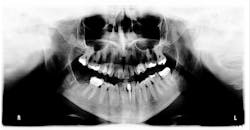

Figure 2: Mandibular arch

Her periodontal probing depths ranged from 2 mm to 6 mm, with as much as 4 mm of recession noted in some areas. Tooth No. 19 had a fractured off DL cusp to the gumline with decay close to the nerve; No. 29 had deep DO decay that would require endodontic treatment, buildup, and a crown to repair or possibly extraction; and No. 31 was unrestorable with buccal decay to the nerve, through the furcation, and at the bone level (figures 1–6). Faced with that treatment plan, she would also need four quads of scaling and root planing with anesthetic. We were able to coordinate the schedule to extract No. 31 directly after her periodontal treatment while she was still anesthetized.